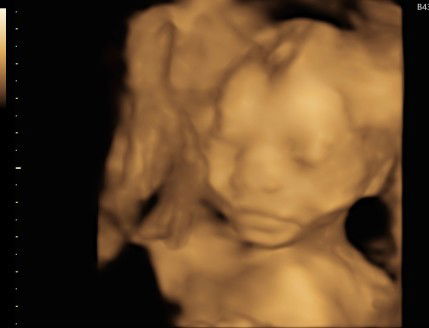

Hasil usg 20w4h

Assalamualaikum, Bunda, mau tanya dong. Semalam usg ke dokter dan katanya normal. Tapi pas sampe rumah baru ngeh sama hasil usg nya. Bagian kepala seperti itu apakah normal? Terimakasih

namanya jg hasil usg bu ☺️ emang suka aneh2. dokter pst tau mana yg normal dan engga.